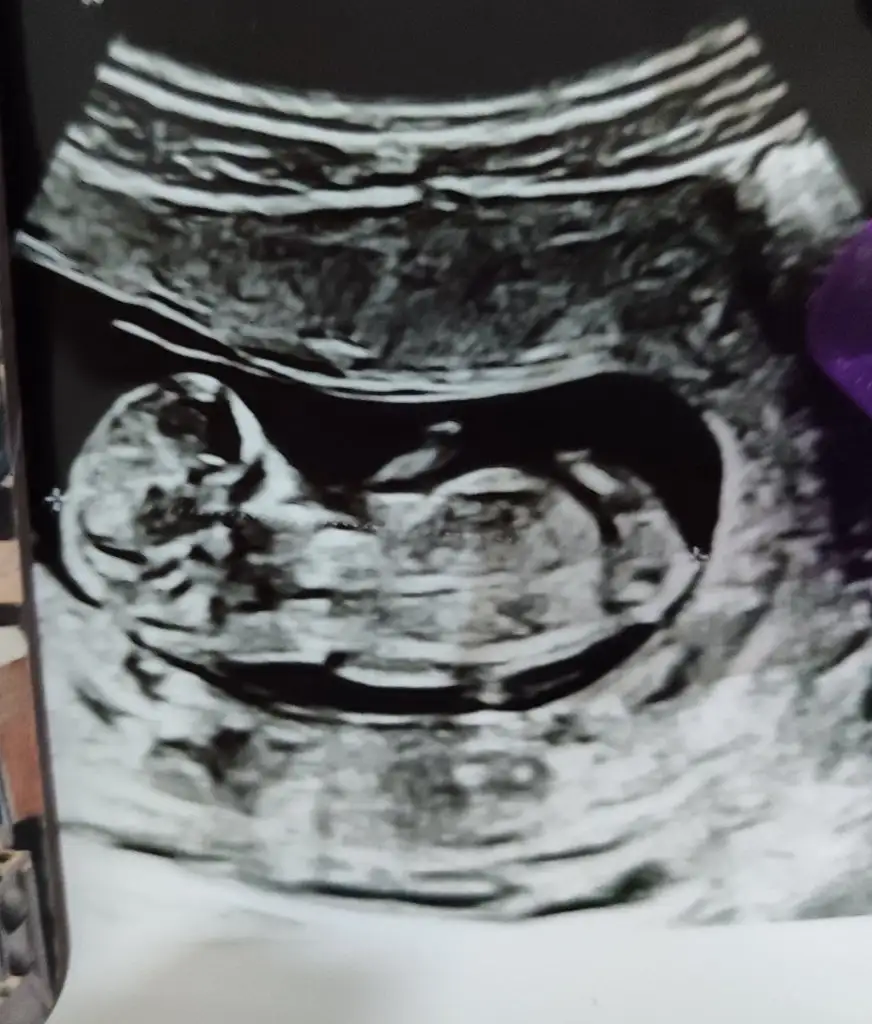

banada bakar mısınız kızlar bebişim sizce kız mı erkek mi?Merhaba ilk doktorum %70 kız dedi değişebilir dedi şuan 14. Haftayım görüntü de bişey söylemedi değişti mi yoksa kız mı? Anlamıyorum![]()

![]()